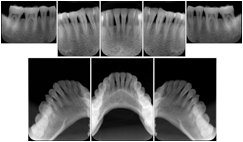

Intra-oral radiography typically involves acquisition of multiple images of various parts of the dentition. Many digital radiographic systems offer customized templates that are used for displaying the images in a study on the screen. These templates may also be referred to as mounts or view sets. The Structured Display Object represents a standard method of encoding and exchanging the layout and intended display of Structured Displays. A structured display object created in this manner could be stored with a study and exchanged with images to allow for complete reproduction of the original exam.

2. A patient requests cosmetic surgery to enhance their facial appearance. The case requires consultation between an orthodontist in New York and an oral surgeon in California. The cephalometric series of 2D projections constructed from a volumetric CT data set that is used for the discussion is arranged by a Structured Display for transfer between the two practitioners.

Cephalometric Series Structured Display

Figure OO-2. Cephalometric Series Structured Display